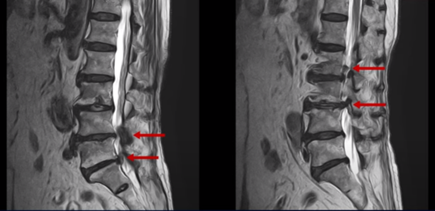

이분의 허리 MRI를 보면 여러 마디에 퇴행성 변화가 있습니다.

우선 5번 1번 마디를 보면 오른쪽으로 디스크도 밀려나와있고 또한 추간공도 좁아져 있는 것이 보입니다. 이걸 협착이라고 합니다.

1년 전부터의 오른쪽 다리 증상은 이 추간공이 좁아져서 생긴 추간공협착증 증상 때문인 것으로 보입니다.